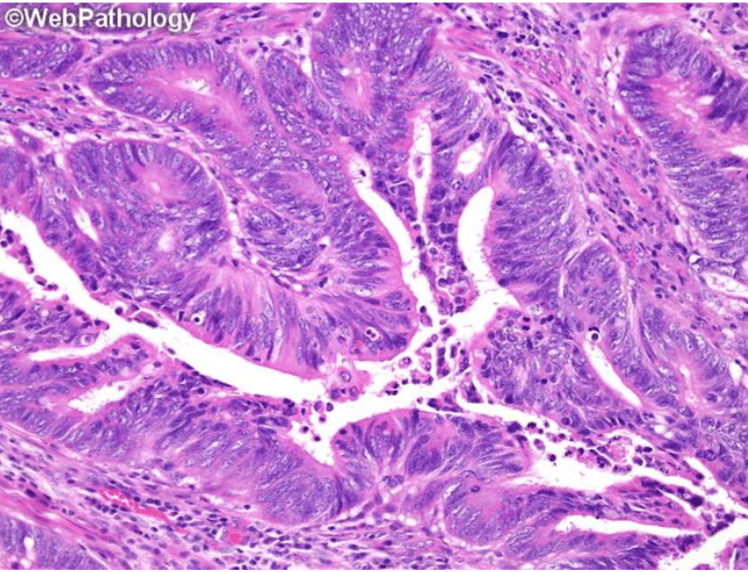

Which image shows malignant colonic mucosa